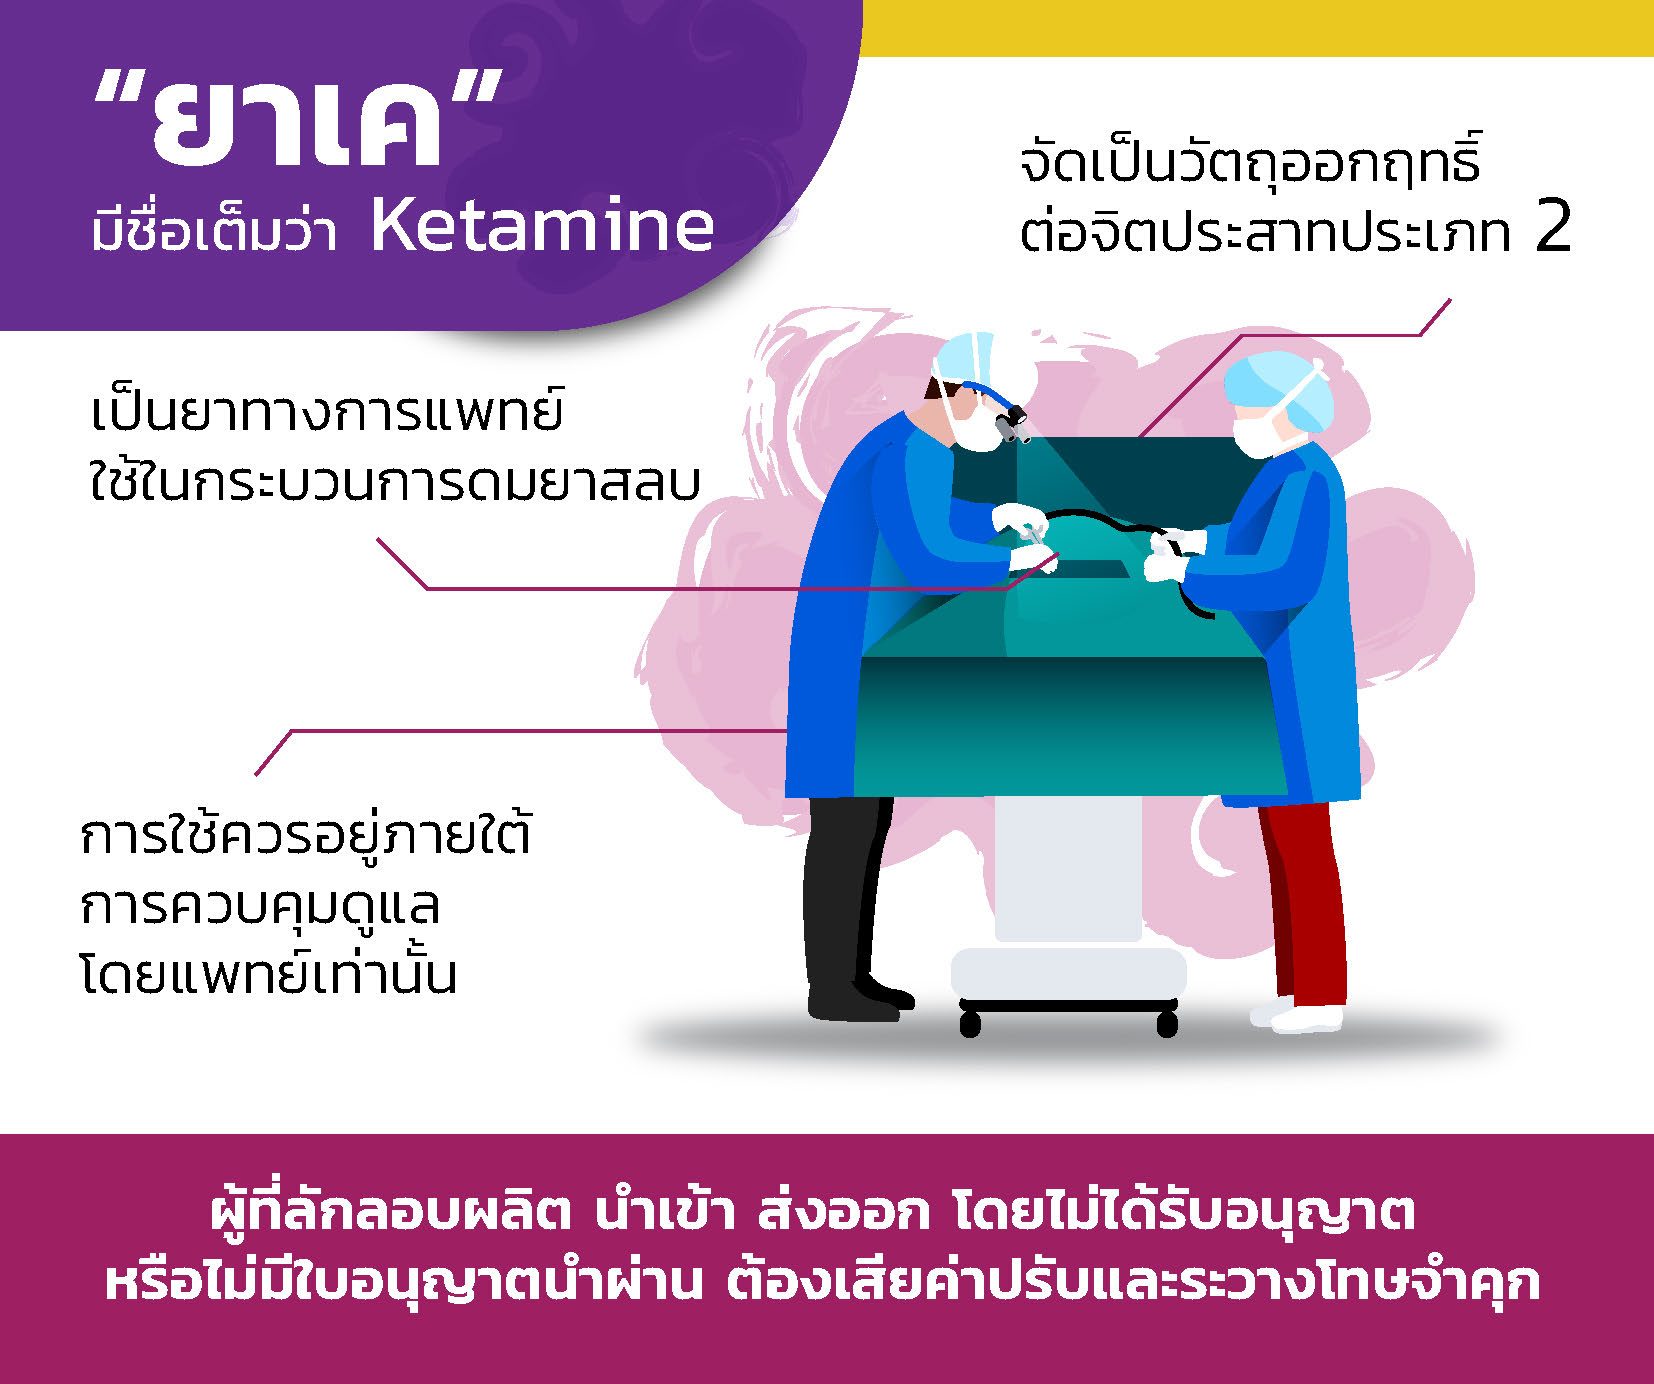

ชาวเน็ตจับผิด “ซาร่า” ภาพอัลตราซาวด์ปลอม เหมือนของ “เซเลน่า โกเมซ” ทำความรู้จัก ‘ยาเค’ จุดเริ่มต้นยานรก ‘เคนมผง’ รพ.ตำรวจเผยเสพแล้วสุดหลอน

ทำความรู้จัก ‘ยาเค’ จุดเริ่มต้นยานรก ‘เคนมผง’ รพ.ตำรวจเผยเสพแล้วสุดหลอน ตำนานแห่งอียิปต์ เรื่องเล่า มัมมี่ (Mummy) – Thailand Working

แพทย์ รพ.ตำรวจ เตือนกรณี ใช้ ‘เคนมผง’ อันตรายถึงชีวิต-ขยายผลแหล่งต้นตอ มัมมี่อียิปต์สัญลักษณ์โบราณของอียิปต์สไตล์แบนเวกเตอร์ภาพประกอบบนพื้น …